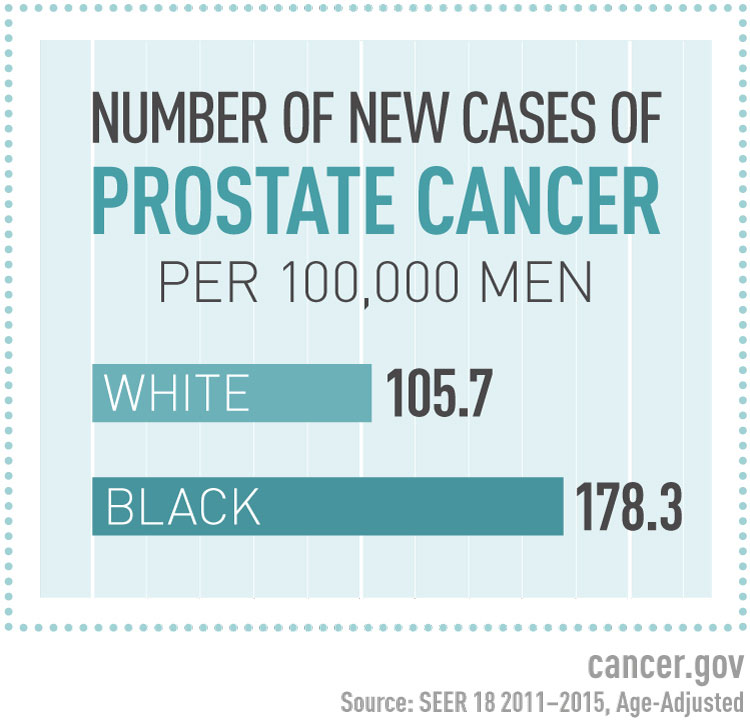

By the numbers: Prostate cancer | Urology

African American Disparities in Low-Grade Prostate Cancer Death …